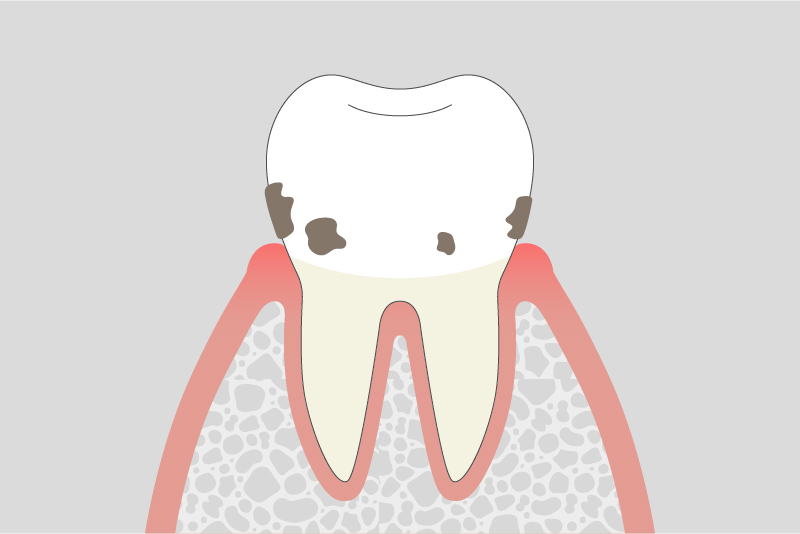

02.

軽度歯周炎

歯周ポケットが深くなり、炎症が歯ぐきの内部に広がります。腫れや出血が続くことがあり、口臭が気になる場合もあります。